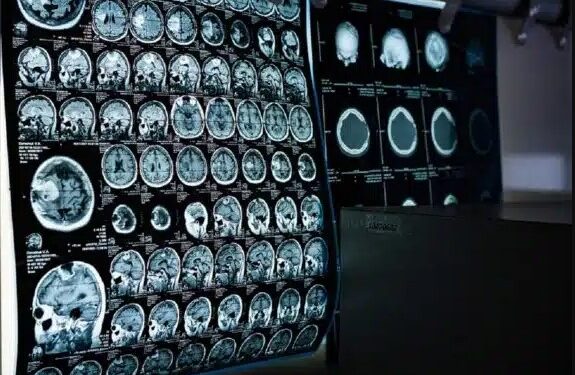

Imagen referencial: Pixabay.es

La RMN es uno de los exámenes requeridos por médicos especialistas para, a través de un campo magnético y onda de radiofrecuencia, obtener imágenes anatómicas tridimensionales y detalladas para detectar diferentes padecimientos como anomalías congénitas, tumores, patologías neurodegenerativas, entre otras. Asimismo, mediante ella se pueden monitorear la funcionalidad de diversos tratamientos.